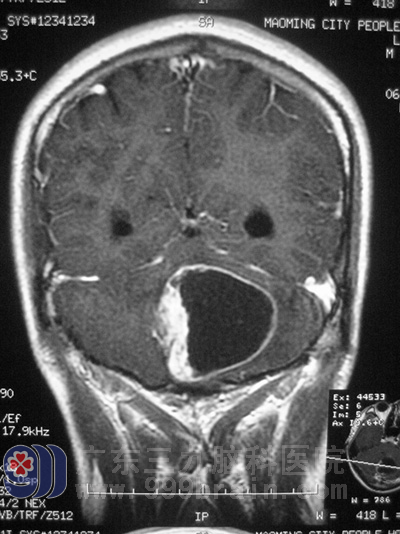

最近几天,阿辉的头痛越来越频繁,清晨起床后头痛更剧烈,并伴有恶心、轻微头晕等症状。到当地医院行头颅CT检查后发现:左小脑及小脑蚓部区占位病变并幕上脑积水。一家人都不愿意相信这个检查结果,于是再次到当地中心医院求证,行头颅MR提示小脑半球占位性病变,怀疑为血管母细胞瘤或小脑星形细胞瘤。但由于肿瘤长的位置较深,肿瘤附近血管丰富,毗邻脑干,因此,当地医院不敢贸然为之手术,并告知阿辉,手术过程稍有不慎将会使他瘫痪或者变成植物人。

手术前